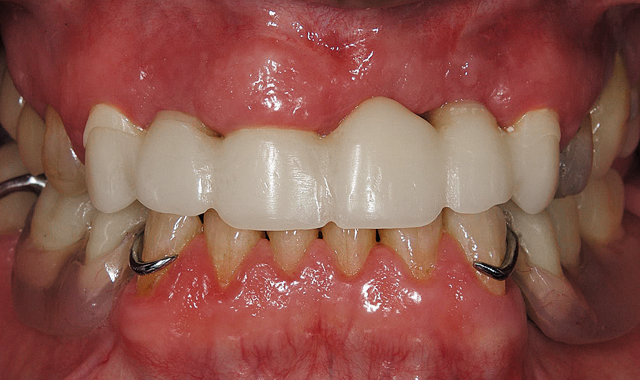

Six units temporary bridge and mandibular partial.

05 The doctor then fabricated temporary removable partials for the patient, and now the patient’s new bite was 100 percent established and ready to be created and transformed into reality (Fig. 5).

The doctor was able to scan the case chairside using the CEREC Omnicam and then sent the scan to my laboratory digitally via the Sirona Connect network. With inLab’s new Software 15 (SW 15), I can now utilize the amazing new biocopy function to perfectly design and replicate the temporary and then send the six-unit case to mill on the inLab MC X5 wet/dry milling unit.